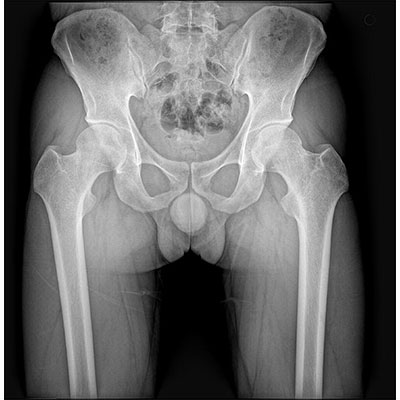

● 采用自主研發(fā)的技術,在保證優(yōu)質圖像的前提下,大大降低X射線劑量,用心呵護醫(yī)護工作者及患者的健康。

● 短曝光時間,便于老年人、兒童、殘疾人進行臨床拍攝。避免這類群體因不能有效控制身體運動等因素造成的運動偽影,提高攝片質量及效率。